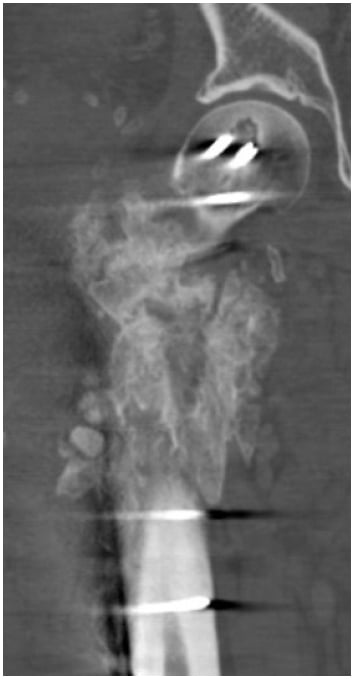

For the next year, the patient completed multiple rounds of antibiotics and underwent several more surgeries. In July 2021, he presented to the emergency department (ED) with persistent complaints of pain in the right hip and a sinus of draining purulence. Computed tomography (CT) revealed a right intertrochanteric fracture nonunion with well-circumscribed fluid collection (Fig. 2); the patient underwent open debridement, hardware removal, fracture stabilization, and antibiotic bead placement (Fig. 3). Deep cultures taken at this time revealed no bacterial growth. Of note, the patient had been maintained on dual antibiotic therapy for 8 weeks prior. Postoperatively, he was maintained on antibiotics and observed clinically and was discharged after 5 days.

Figure 2: X-rays of the right hip at presentation; the patient had erythema and drainage from the previous surgical incision.